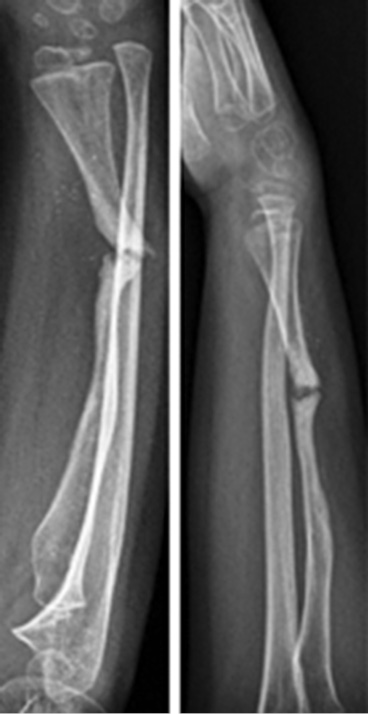

Через 10 дней после выписки из больницы пациент вновь обратился в отделение неотложной помощи с нарастающей болью в ноге, откуда была получена кость. Установлен диагноз местной гематомы, вызванной поражением межкостной артерии. В связи с этим проведена экстренная сосудистая операция для дренирования гематомы и закрытия поражения артерии. В феврале 2016 г., всего через 10 дней после последней операции, у пациента снова появилась боль в ноге. Было решено обратиться за советом в другой институт, в котором диагностировали псевдоаневризму пораженной артерии, по поводу которой проведена новая экстренная сосудистая операция. Между тем рентген не показал консолидации трансплантата в предплечье. После неудачи повторного введения факторов роста костного мозга в декабре 2016 г. выполнена новая операция с санацией очага несращения и трансплантацией трупной кости с фактором роста костного мозга, стабилизированной спицами Киршнера (рис. 5, 6).

Рис. 5. Отсутствие на рентгенограмме консолидации аутологичной малоберцовой кости

Рис. 6. Рентгенограмма после санации очага несращения и трупный костный трансплантат с костномозговым фактором роста, стабилизированный спицами Киршнера